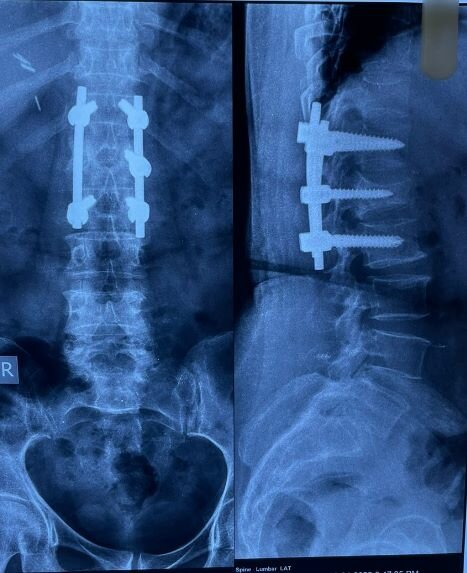

Successful L1 Burst Fracture Procedure by Dr. Sudheer Pathu

Dr. Sudheer Pathu, a skilled Consultant Orthopaedic Spine Surgeon, successfully performed a procedure for a 65-year-old female patient named Venkatamm...